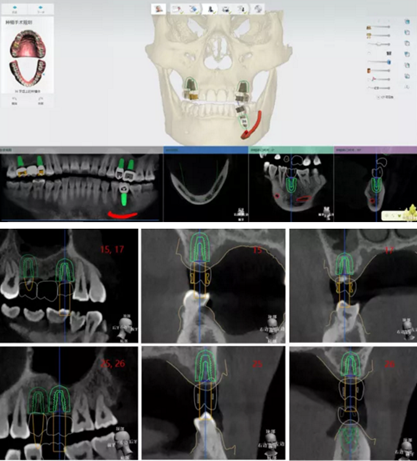

植體植入設(shè)計(jì)

設(shè)計(jì)植入5顆種植體

查看種植體螺絲通道穿出虛擬修復(fù)體的位置。

查看種植體在牙槽嵴頂穿出位置。

規(guī)劃種植導(dǎo)板